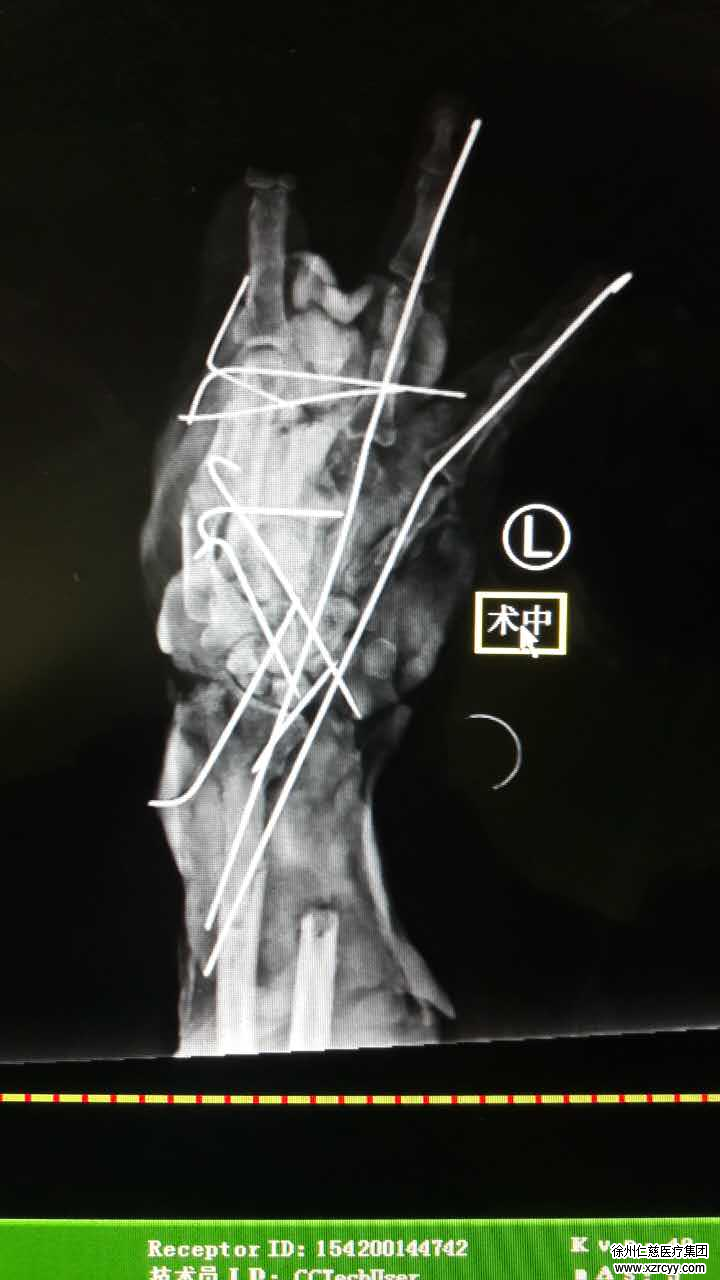

原大姐的左手严重畸形,中指离断,骨外露,左前臂皮肤烫伤伴缺损,伤情远远比想象中严重。事不宜迟,必威官方首页官网betway手外科胡俊生主任接诊原大姐后,对其紧急进行了“左上肢清创血管神经肌腱修复骨关节内固定手术”。

就毁损的严重性,betway在线登陆胡俊生主任介绍说:“目前皮肤软组织缺损,骨外露,属于那种最难处理的外伤,加之还有烫伤,就目前情况来说,原大姐还需要进行多次手术,这期间很容易感染。”